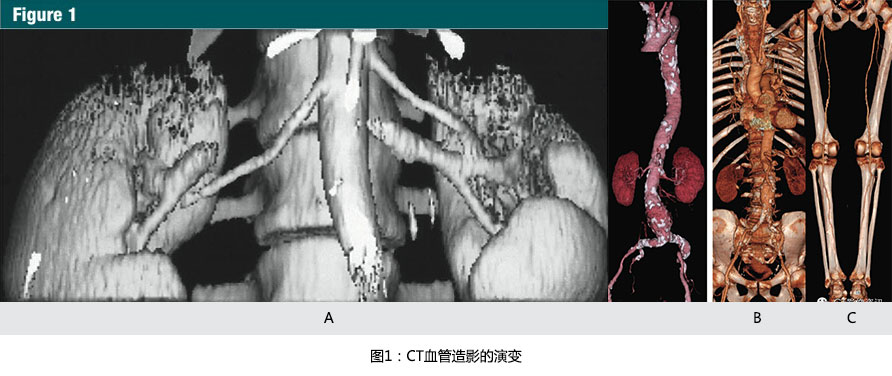

在1991年到1998年,由于單排螺旋CT的掃描速度限制了CTA進入到各個不同的血管領域。采用大于1的掃描螺距之前,一個層厚3mm,30秒的掃描,最大覆蓋的范圍是9cm,因此,限制了在頸外動脈(10)、Willis環(huán)(11),腎動脈(12,13)(圖 1a)及近端腹主動脈(13)中的早期應用。

From 1991 to 1998, single-detector row spiral CT technique limitedclinical CT angiography to discrete vascular territories. Prior to the introduction of scan pitch values greater than one, a scan with 3-mm nominalsection thickness provided a maximum of 9 cm table travel in 30 seconds andthus limited initial applications to the extracranial carotid arteries (10),the circle of Willis (11), the renal arteries (12,13)(Fig 1a), and the proximal abdominal aorta(13).

1998年推出的早期多排探測器CT具有4排探測器和0.5s的旋轉時間,對于相同層厚,單位時間增加了8倍的容積覆蓋范圍(8,23)(圖 1b,1c)。

Early multi-detector row CT scanners introduced in 1998 had four detector rings and were capable of 1/2-second gantry rotations, effectively multiplying volume coverage per unit time 38 at the same section thickness (8,23)(Fig 1b, 1c).

摩爾定律也直接成為CT血管造影(CTA)最終臨床應用的推動者:因為一層接著一層的CTA圖像并不有效和直觀,可視化的CT血管造影包括表面遮蓋顯示,最大密度投影,和容積再現(VR)(圖1b,1c)。

Moore's law is also directly responsible for the final enabler of clinicalCT angiography: Because section-by-section inspection of CT angiographic imagesis neither efficient nor intuitive, visualization of CT angiography studies employs shaded surface displays, maximum intensity projections, and volume rendering (Fig 1b, 1c).

(A):1991年12月獲得的腎動脈CT血管造影圖像。9厘米的縱向覆蓋,采用3mm的準直線束需要30秒螺旋掃描時間。當時,表面遮蓋技術是唯一的三維顯示手段。最大密度投影和容積再現成像需要在高度專業(yè)的計算機系統(tǒng)上進行脫機處理(參考文獻13)

(B):隨著1998年的四排螺旋CT的引進,使主動脈-髂動脈系統(tǒng)(從胸廓入口開始直到腹股溝)作為一個整體僅通過一次圖像采集并成像成為了可能。容積再現技術所展示的CTA圖像,使用4x2.5mm的螺旋掃描模式在28秒內掃描完成。圖片充分顯示了主-髂動脈鈣化和腹主動脈瘤(參考文獻8)

(C):2001年使用容積再現技術展示的CTA圖像,使用16 x1.25毫米螺旋掃描模式,僅用了21秒的時間,就完成了從顱底至踝的動脈系統(tǒng)掃描,離1991年第一例螺旋CT的CTA成像只隔了10年,但是CT的掃描速度則增加了近25倍。